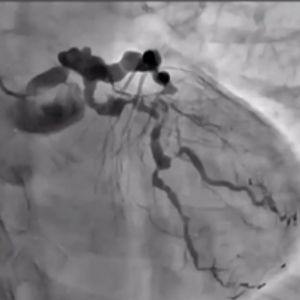

In the mid-to-late 2000s, the retrograde approach was introduced, leveraging collateral channels for wire crossing, significantly improving the success rates of CTO-PCI. This technique gained widespread attention due to the expertise of Japanese operators, elevating the global recognition of Japan's contributions. However, the use of delicate collateral channels posed challenges, particularly for less experienced interventional cardiologists, leading to complications such as perforations. Consequently, enthusiasm for CTO-PCI waned in Western countries, where its perceived lack of reproducibility kept it relegated to the realm of mastery-level procedures.

A new wave of technological innovation emerged in the late 2010s with the introduction of the 3D wiring technique. Developed by Dr. Atsunori Okamura of Sakurabashi Watanabe Hospital, this method enabled three-dimensional visualization of wires within occluded lesions, allowing precise manipulation by observing the movement of the wire tip in three dimensions. This rational approach transitioned CTO-PCI wiring from a skill dependent on tactile sensation to one guided by scientific observation.

The 3D wiring technique was further refined by expert operators across Japan, eventually establishing Tip Detection Antegrade Dissection Re-entry (TD-ADR) as a new standard in CTO-PCI. TD-ADR reignited global interest in CTO-PCI by providing a more systematic and reproducible methodology. More recently, HydroDynamic Contrast Recanalization (HDR) has emerged as a technique for performing antegrade CTO-PCI, leveraging the synergistic use of contrast microinjections and polymer-jacketed wires to further expand the technical options available for CTO-PCI.

Compared to conventional approaches to CTO-PCI, the emergence of TD-ADR and HDR has significantly reduced costs, procedure times, and complication risks. These advancements inspire confidence that CTO-PCI, often referred to as the "last frontier" of PCI, could become a fundamental treatment for totally occluded lesions.